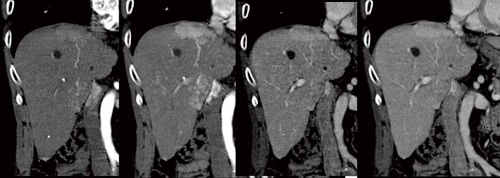

1.MPR

多くの施設でaxial像とともにMPR(MultiPlanner Reconstruction)像の提出がルーチンワークとなりつつある。MPR像は,腫瘍の進達度評価,病巣の位置確認,進展度,病変と脈管との関係など多くの情報を得ることができる(図5)。また,ワークステーションを自社開発しているため, AWとCTに搭載されているワークステーション機能の操作性が統一されている。

図5 ダイナミック検査における時相ごとのMPR像 |